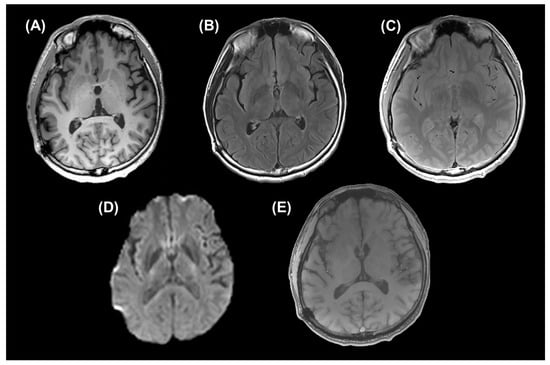

3.1. Conventional MRI